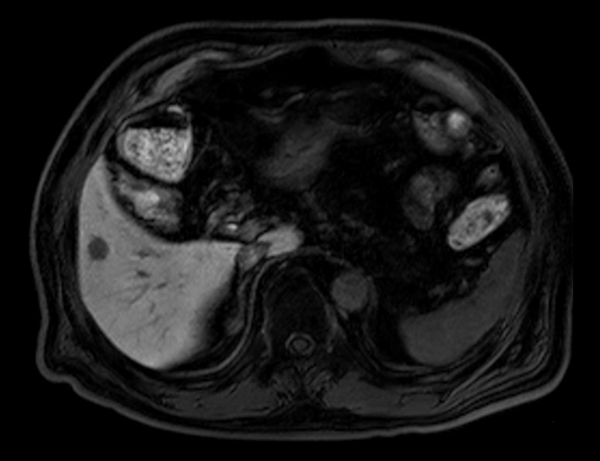

Axial Diffusion (b800)